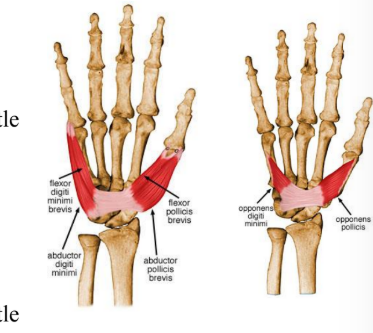

Four thenar muscles

Abductor pollicis brevis

Flexor pollicis brevis

Opponens pollicis brevis

Four hypothenar muscles

Abductor digiti minimi

Flexor digiti minimi

Oppenens digiti minimi

Thenar muscles

ORIGIN | INSERTION | ACTION | INNERVATION | |

Abductor pollicis brevis | Flexor retinaculum and tubercle of scaphoid and crest of trapezium | Lateral of base of proximal phalanx of thumb | Abducts the thumb at metacarpophalangeal and carpometacarpal joint | Median nerve |

Flexor pollicis brevis | Superficial head- flexor retinaculum and crest of trapezium Deep- trapezoid and capitate bone | Lateral side of base of proximal phalanx | Flexes thumb | Median nerve |

Opponens pollicis | Flexor retinaculum and crest of trapezium | Lateral side of 1st metacarpal | Draws 1st metacarpal to oppose thumb | Median nerve |

Hypothenar muscles

ORIGIN | INSERTION | ACTION | INNERVATION | |

Abductor digiti minimi | Pisiform bone | Medial side of base of proximal phalanx of little finger | Abducts little finger | Deep branch of ulnar nerve |

Flexor digiti minimi | Hook of hamate a/nd flexor retinaculum | Medial side of base of proximal phalanx of little finger | Flexes little finger at metacarpophalangeal joint | Deep branch of ulnar nerve |

Opponens digiti minimi | Hook of hamate and flexor retinaculum | Medial border of shaft of 5th metacarpal | Draws 5th metacarpal anteriorly and rotates it laterally, opposes thumb | Deep branch of ulnar nerve |